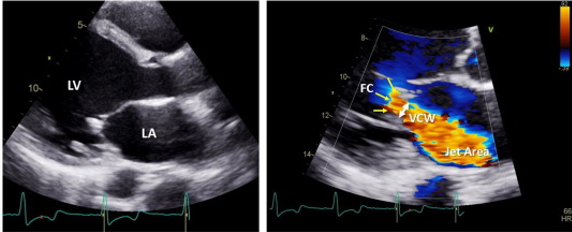

how does color doppler indicate mitral valve regurg?

vena contracta

jet area

flow convergence

in what view is vena contracta measured?

PLAX (perpendicular to jet)

how do you measure vena contracta ?

narrowest portion of jet as it emerges from the orifice